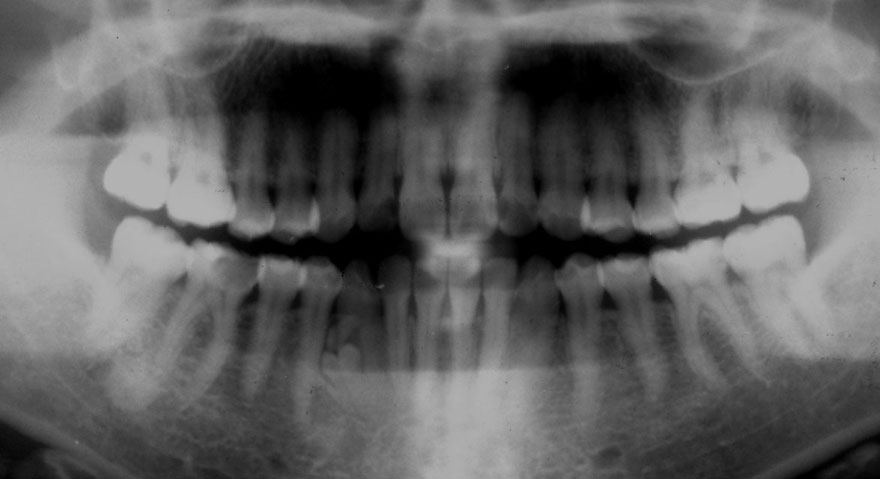

初診時 36歳 女性 平均歯槽骨喪失量:2.70mm

30年後 66歳

平均歯槽骨喪失量:3.26mm

30年間喪失量:-0.55mm

年間喪失速度:-0.018mm

(ケア頻度:3.01ヵ月ごと)